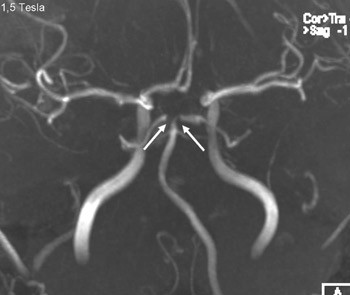

En person i 20-årene med kjent migrene med aura fikk infarkter i høyre arteria cerebri media og begge anteriorgebet (figur 1 viser en magnettomografidiffusjonsvektet serie). Cerebral computer- og magnettomografi med blodstrømsangiografi (MRA) etter innleggelse viste upåfallende strømning uten tegn til disseksjon eller vaskulitt. Hemikraniektomi ble nødvendig etter utvikling av malignt hjerneødem. MR-angiografi i narkose dagen etter operasjonen viste åpne arterier (figur 2 viser en åpen carotistopp (hvit pil), normal basilaristopp (rød pil) samt en ikke-lukket Willis’ sirkel, som er en anatomisk normalvariant (stjerner)). Testing på sentralstimulerende substanser, antikardiolipin, antinukleære antistoffer, nevronantistoffer og tumormarkører ga negative funn. Transøsofageal ekkokardiografi viste et minimalt patent foramen ovale, lite sannsynlig relatert til hendelsen, ifølge kardiolog. Pasienten utviklet alvorlig hjernestammeaffeksjon og MR-angiografi viste forsnevring i arteria basilaris posterior-forgreningen (pilene i figur 3). Arterielle karspasmer ble retrospektivt mistenkt. Den første mistenkte karspasmen i høyre media-/anteriorforgreningen forble udokumentert. Den andre i basilaris-/posteriorforgreningen ble dokumentert postoperativt (pilene i figur 3). Bildene av flere nytilkomne infarkter i bakre kretsløp vises ikke. Tre uker etter hemikraniektomi var ny angiografi normalisert (figur 4).